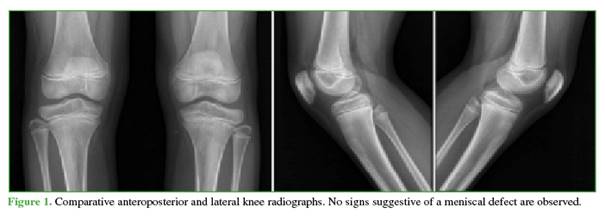

A 14-year-old male, with asthma and active in sports, presented to the Emergency Department with a two-week history of left knee pain sustained during soccer training. He had persistent pain associated with limping and intermittent locking. After initial evaluation and radiographs (Figure 1), outpatient management was chosen under the suspicion of a sprain. Symptoms decreased slightly, and locking ceased.